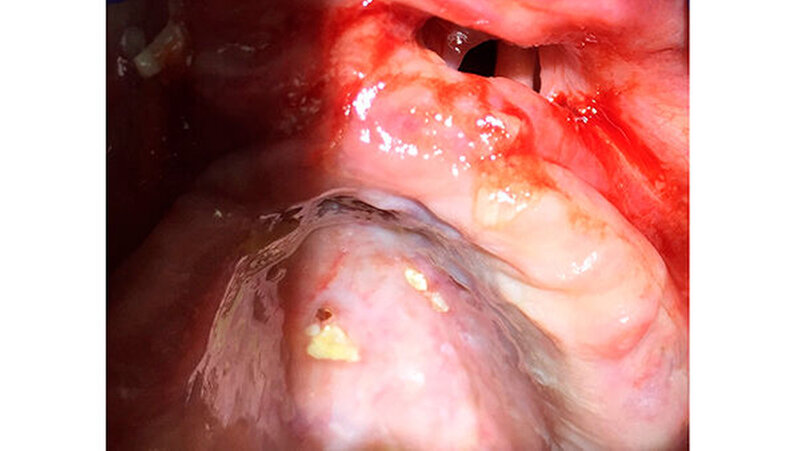

Der perforierte Gaumen

Der Gaumen war perforiert, was den anfänglichen Verdacht einer Mund-Antrum-Verbindung (MAV) bestätigte. Mit dem Verdacht auf eine Wegner`sche Granulomatose überwies die Zahnärztin die Patientin zum Internisten, der in der Blutuntersuchung jedoch nur leicht erhöhte ANA- und ANCA-Werte feststellen konnte, die den Verdacht auf eine Autoimmunerkrankung nicht bestätigten.

Die Patientin wurde dann über acht Wochen mit Clindamycin behandelt. Eine in der Zahnarztpraxis erfolgte plastische Deckung der MAV platzte nach zwei Tagen post operationem wieder auf. Ihr Allgemeinzustand verbesserte sich trotzdem erheblich. Im Unterschied zu vorher konnte sie den Weg vom Wartezimmer in den Behandlungsstuhl selbstständig gehen.